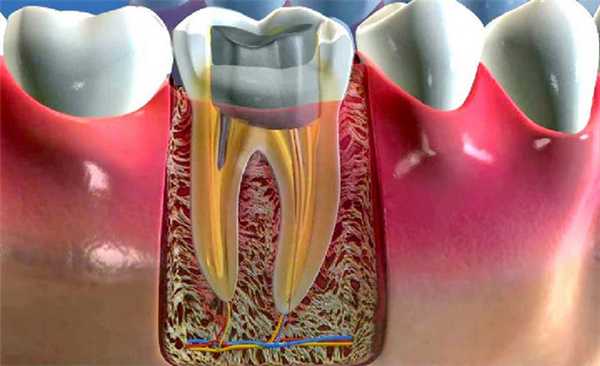

Вкладка является цельнолитым изделием, внешне напоминающим миниатюрный зуб. Микропротез состоит из верхней части (культи, обточенной под коронку) и «ножек» в виде штифта, которые интегрируются в корневой канал. На культю (отсюда и название вкладки) с помощью специального цемента крепят искусственную коронку.

Почему культевая вкладка лучше зубного штифта

Развитие современных медицинских технологий в области стоматологии позволяет установить коронку, когда от резца или моляра практически ничего не осталось кроме корня. Для этого проводят процедуру восстановления культи или установки культевой вкладки. Вкладка состоит из двух частей: одна часть полностью повторяет культю зуба, а другая представляет собой штифт. Процедуру проводят с использованием стоматологических композитов.